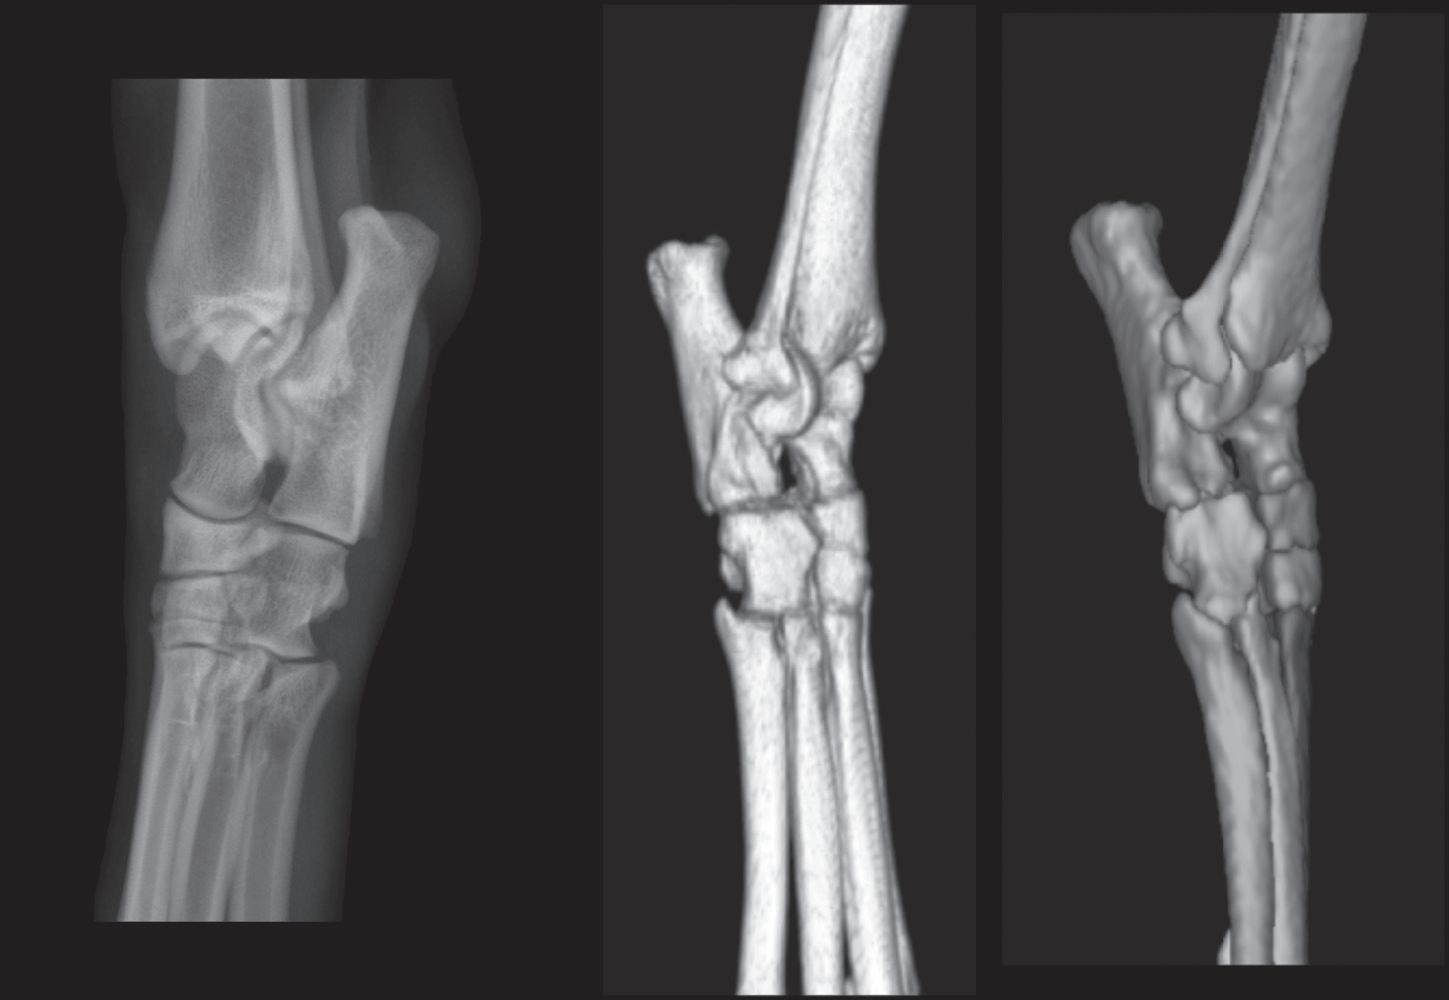

Figure 1-14. The left panel is a dorsal 45-degree lateral-plantaromedial radiograph of a canine tarsus. The middle panel is a three-dimensional rendering of a normal right canine tarsus as seen from the perspective of the x-ray beam when making a dorsal 45-degree lateralplantaromedial radiograph. The right panel is identical to the middle panel, but where each bone has been colorized (see Color Plate 4). Colorizing makes it easier to comprehend the extent of overlap. It is important to note that the dorsal surface of the radiograph is oriented to the viewer’s left; this is standard policy. The dorsal surfaces of the three-dimensional models are oriented to the viewer’s right because the models are anatomically correct, and this is the orientation that the radiographer would see. Note in the radiograph that the only edges of the tarsal bones where the surface can be evaluated are the dorsomedial and plantarolateral edges.